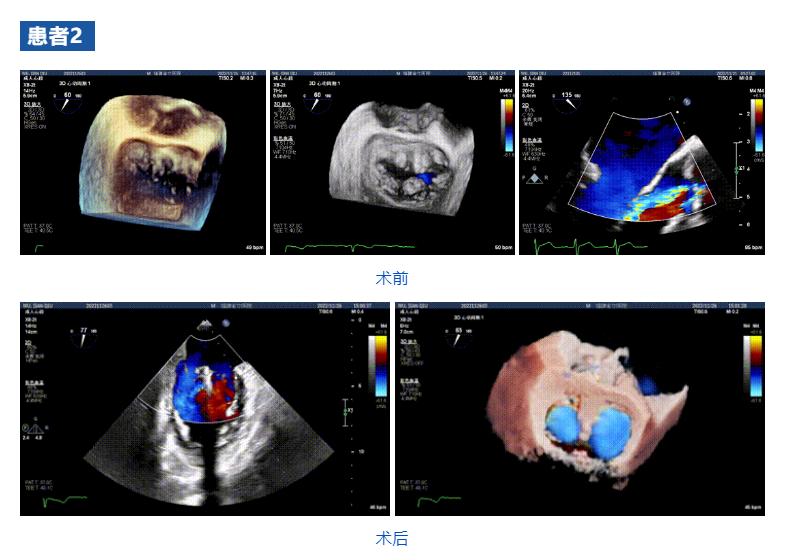

接受治療的三例患者均為器質(zhì)性重度二尖瓣反流(DMR)患者,術(shù)前超聲提示二尖瓣后葉脫垂伴4+反流,左室舒張功能減退。郭延松教授攜同團(tuán)隊(duì)成員陳新敬副教授和洪景宣、方明程、楊清勇主治醫(yī)師、心外科丁杭主任以及超聲科賴(lài)寶春、葉振盛主治醫(yī)師共同進(jìn)行病情討論??紤]到患者高齡、基礎(chǔ)疾病多、STS評(píng)分高,為外科手術(shù)極高?;颊?,不適合進(jìn)行外科開(kāi)胸二尖瓣手術(shù),因此決定為患者實(shí)施經(jīng)導(dǎo)管緣對(duì)緣修復(fù)介入術(shù)(JensClip經(jīng)導(dǎo)管瓣膜夾系統(tǒng))。

在浙江大學(xué)醫(yī)學(xué)院附屬第二醫(yī)院王建安教授團(tuán)隊(duì)的支持下,手術(shù)經(jīng)股靜脈-房間隔入路,采用全身麻醉插管,在TEE和DSA引導(dǎo)下完成房間隔穿刺。置入JensClip瓣膜夾系統(tǒng)后,在左房調(diào)整瓣膜夾的位置和軸向,后進(jìn)入左室,在TEE引導(dǎo)下捕捉二尖瓣前后瓣葉,并關(guān)閉瓣膜夾。經(jīng)TEE反復(fù)確認(rèn)手術(shù)效果后最終鎖定并釋放瓣膜夾。術(shù)后即刻超聲顯示瓣膜夾位置穩(wěn)定,功能良好,二尖瓣反流由術(shù)前4+減少至微量,手術(shù)圓滿成功。